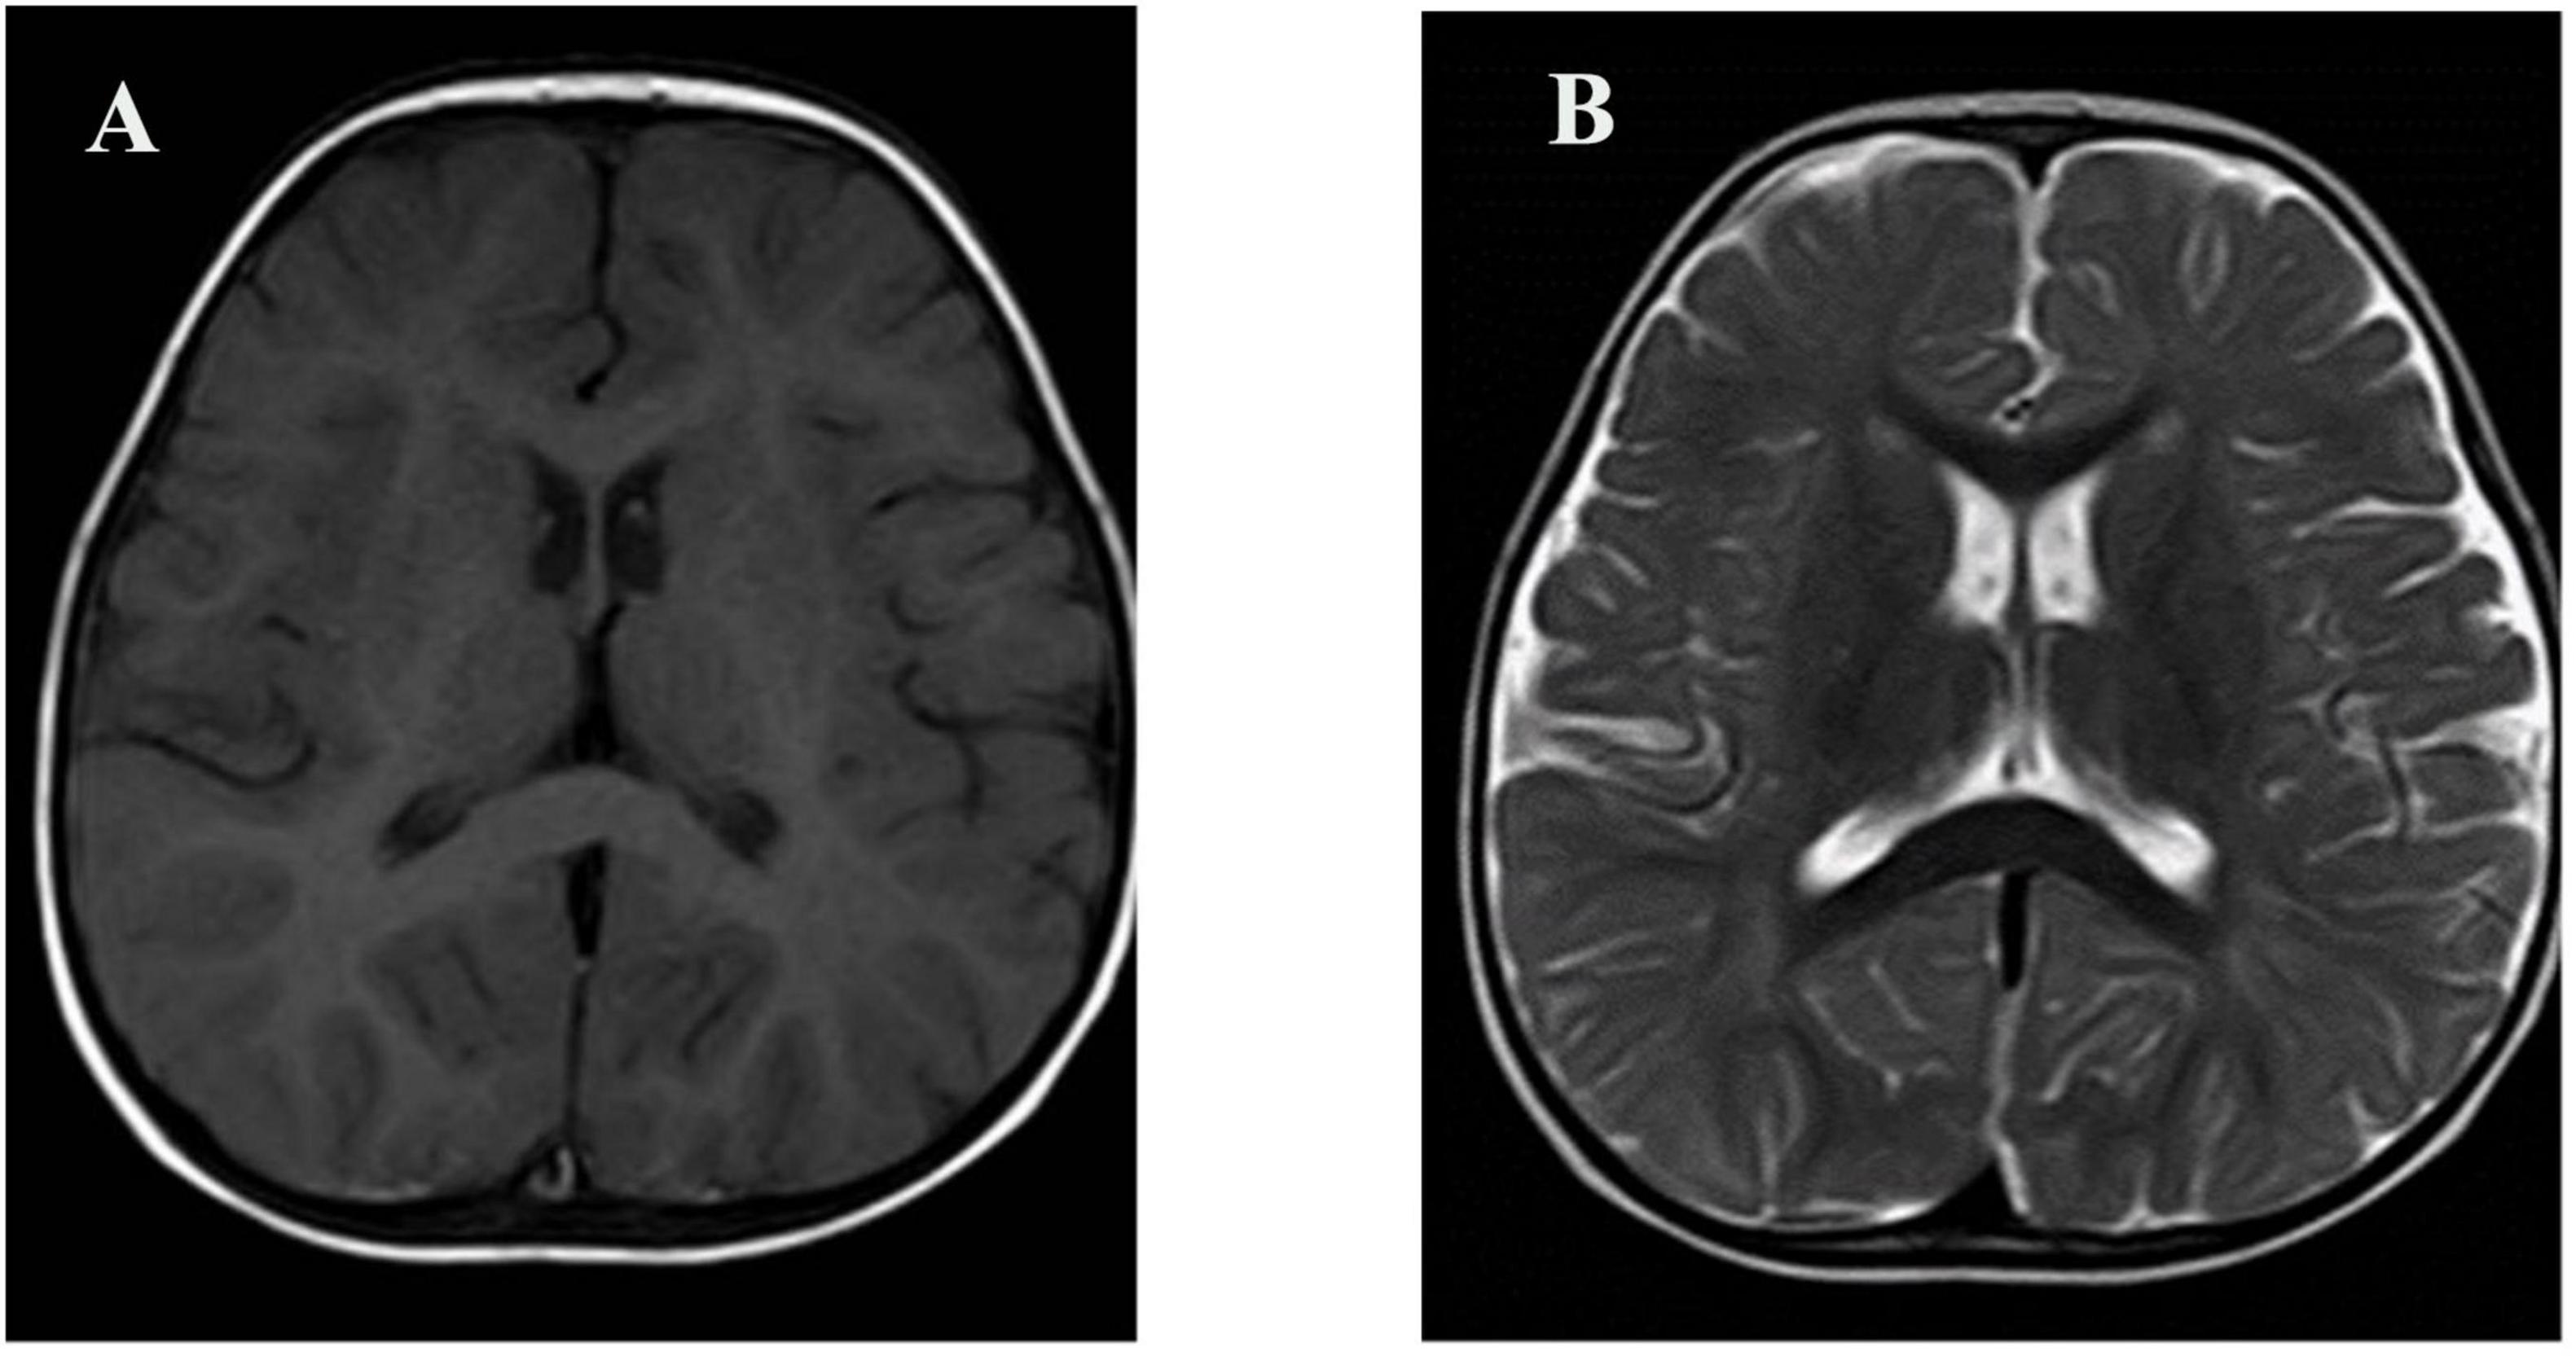

At 11 months of age, he presented with his first seizure during a febrile illness, with a body temperature of 38°C–39°C. During this episode, seizures consistently occurred when the body temperature exceeded 38°C, with a seizure latency of within 1 h from the time the temperature rose above this threshold. The seizure was generalized tonic-clonic in type and lasted 1–3 min. During the same febrile episode, he experienced five to six similar seizures within a short period. He was admitted to our department on 4 November 2021, for evaluation. Brain magnetic resonance imaging was unremarkable (Figure 1). Interictal electroencephalography demonstrated mildly slowed occipital background activity (6–7 Hz theta rhythm with intermixed low-amplitude fast activity) during wakefulness, and sparse sleep spindles with occasional left parietal–posterior temporal sharp–slow wave complexes during sleep (Figure 2). Routine laboratory tests, metabolic screening, cardiac ultrasound, and electrocardiogram were all within normal limits. Developmental assessment using the Gesell scale at 11 months of age revealed a global developmental quotient of 73, with scores of 60 for gross motor (able to roll over and sit without support, able to pull to stand with assistance, but unable to stand independently), 53 for fine motor (immature pincer grasp, limited ability to transfer small objects between hands), 70 for cognitive (recognizes familiar people, responds to name, engages briefly with simple toys), 73 for language (produces several babbling sounds and 2–3 single meaningful words, without combining words), and 70 for social skills (maintains eye contact, smiles responsively, responds to social cues from caregivers, but shows limited interaction with peers). Complex febrile seizures were suspected, and the patient improved with symptomatic treatment and was discharged after three days.

Figure 1. Brain MRI of the patient. (A) Axial T1-weighted image; (B) Axial T2-weighted image. No structural abnormalities were observed.